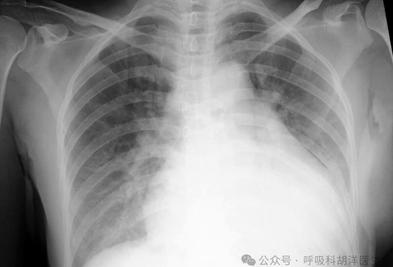

心脏不好关肺什么事,殊不知心肺不分家,肺部的恶疾居然与心有关。 原创 胡洋大夫 呼吸科胡洋医生 心肺是两个非常亲密的器官。形象地说,心脏在肺的怀里。心脏的血液不是直接从右侧流入左侧,而是从右心流入肺部,然后流回左心。因此,心肺不仅是相互帮助的关系,也是生病时相互联 2025-05-21